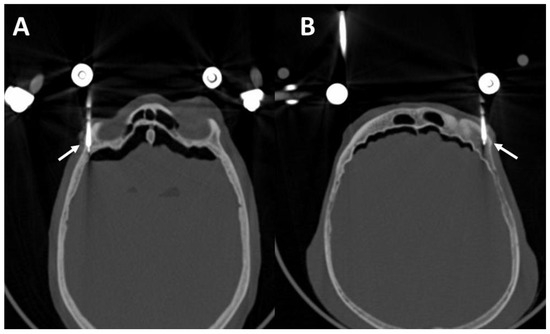

3.4. Postoperative Results in the CT Scans

4.2. Post-Operative CT Scans